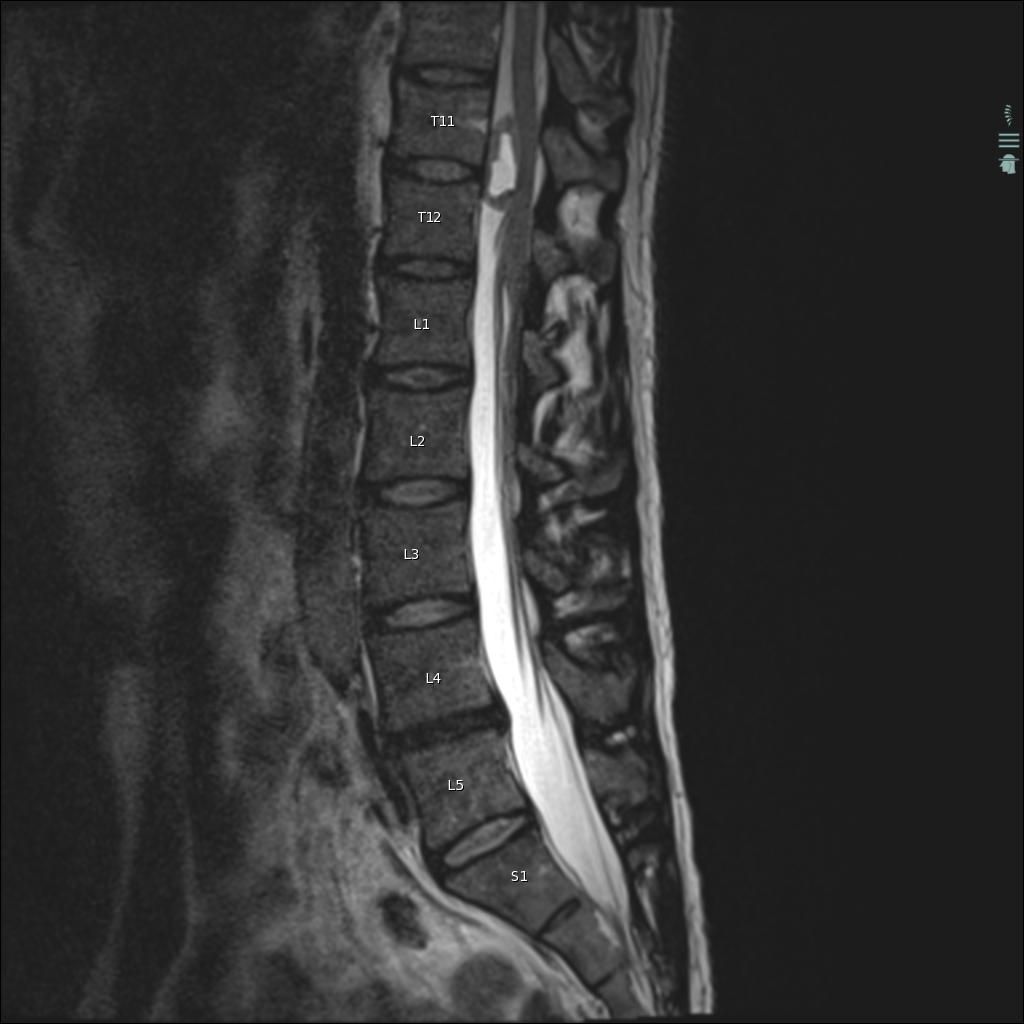

Can you diagnose this patient with low back pain, right lower extremity paraesthesias, and incontinence?

Case History: 40-year-old man with low back pain, right lower extremity paraesthesias, and incontinence. He presents 10 days later with worsening pain.

What is your diagnosis?